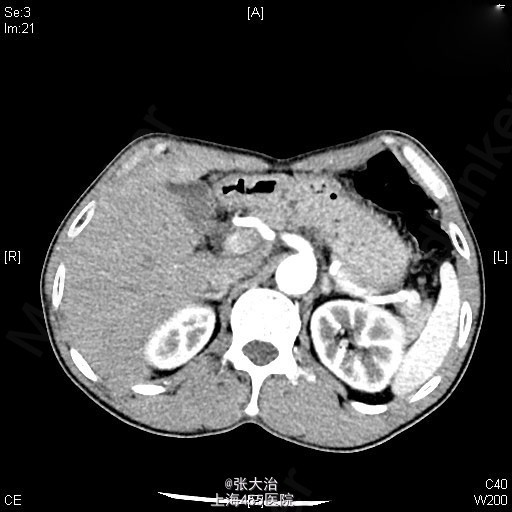

查体:神志清晰,精神尚可,呼吸平稳,营养中等,表情自如,发育正常,自主体位,应答流畅,查体合作。全身皮肤无黄染,无肝掌、蜘蛛痣。全身浅表淋巴结无肿大,无明显贫血貌,左锁骨上淋巴结(-);腹部平坦,未见肠型或胃蠕动波,未见腹壁静脉曲张;全腹软,无压痛、反跳痛、肌紧张。肝脾肋下未及,包块未及;移动性浊音(-),肠鸣音正常,每分钟约3次,不伴高调音、气过水声。 2014-4-10某人民医院就B超(92301):肝囊肿,左肝内胆管扩张;MRI(1697647):肝门区病变可能伴左肝内胆管扩张。 2014-4-22某人民医院MRCP(68941):肝门处占位伴肝内胆管扩张,考虑胆管细胞癌可能大,肝多发囊肿。 肝动脉CTA、门脉CTV、肝静脉CTV、下腔静脉CTVCT【2014-05-05 我院】 :肝门区MT,肝左、右动脉及门脉主干、左支受侵;肝及双肾小囊肿。 上腹部平扫+增强+DWI+MRCPMRI【2014-05-06 我院】 :肝左叶MT(胆管细胞型机会大)伴肝左叶胆管扩张,门脉受侵;肝、双肾小囊肿。 肝脾及门脉;胆(含胆总管);肾+输尿管;胰超声【2014-05-05 我院】 :超声造影:肝门部偏左侧实质占位--考虑肝门部胆管MT,侵犯门脉左支可能;肝左叶胆管扩张;右肾囊肿 肝脏超声造影超声【2014-05-05 我院】 :超声造影:肝门部偏左侧实质占位--考虑肝门部胆管MT,侵犯门脉左支可能;肝左叶胆管扩张;右肾囊肿 肝脏术后(检查胸水、腹水、手术区、膈下)超声【2014-05-20 我院】 :右侧胸腔少量积液;腹水